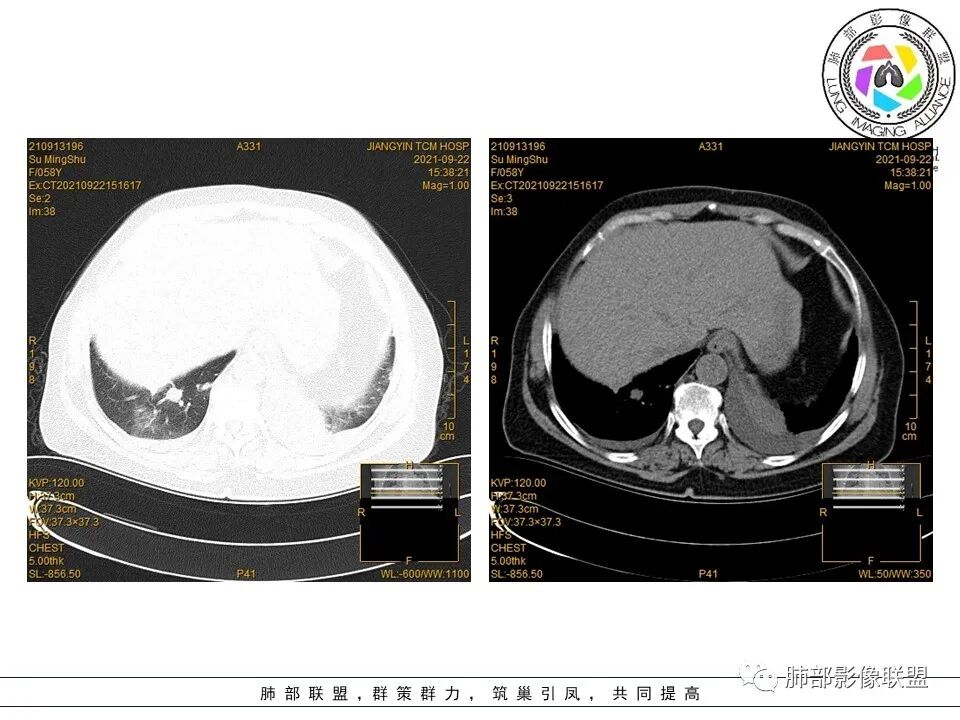

急性病程,处理腊肉吸入热蒸汽。双肺多发大小不等片状,团片,结节影,边缘部分模糊见磨玻璃晕影,部分见支气管穿行,双侧胸腔积液。考虑感染性病变;1.真菌可能大(曲霉、毛霉)。2.不典型肺炎,病毒或衣原体感染。3.淋巴瘤待排(临床病程不符)

双肺多发大小不等结节状及斑片状高密度灶,边缘部分模糊,部分见支气管穿行,双侧胸腔积液,急性发病,糖尿病,考虑感染,金葡、毛霉,结核,淋巴瘤。

中年女性,咳嗽咳痰伴发热5天,急性病程,血象白细胞和中性粒细胞轻度升高,CRP明显升高,降钙素原不高。一型呼衰。双肺野多发结节影,团块影,随机分布,支气管血管束及胸膜下都有,结节边缘模糊,有支气管充气征,团块影边缘平直,支气管进入后截断。双侧少量胸腔积液,考虑感染性疾病,血行播散,金葡菌肺炎?肺克(降钙素原不高)等,鉴别血管炎,淋巴瘤?

中年女性患者,咳嗽咳痰伴发热5天,体温38.5℃,低氧血症,白细胞,中性粒细胞,CRP,血沉等增高,胸部CT:双肺多发斑片结节影,总体沿支气管血管束分布,部分结节见支气管穿行,双侧胸腔积液,左侧偏多,考虑:淋巴瘤可能,鉴别,血管炎,转移瘤,

女性, 57,咳嗽咳痰伴发热5天入院。CT示双肺多发斑片、团状,结节状影,支气管血管束分布,部分病灶内见支气管穿行,双侧胸腔积液,考虑为淋巴瘤可能

老年人,发热,咳嗽,双肺多发结节及团块影,部分位于胸膜下,部分边缘模糊,内见支气管穿行,双侧胸腔积液,发热入院,考虑1.感染(细菌?真菌?),2.淋巴瘤,鉴别血管炎。

双肺内多发团块影,呈支气管血管束走形分布,边界模糊,其内可见支气管穿行,支气管似有扩张。双侧胸腔积液。纵隔内未见明显肿大淋巴结。考虑淋巴瘤,血管炎鉴别。

双肺可见多发大小不等的结节及团块状高密度影,部分沿支气管束分布,部分病变内见支气管穿行,局部管壁凹凸不平,双肺上叶及右肺中叶在结、团状影之间内夹杂片状磨玻璃及结节状(腺泡)高密度影,界不清。老年,男性,5天前吸入病史,血氧饱和度降低,炎性指标升高,考虑二元论,淋巴瘤+HP。双侧胸腔积液。

老年女性,咳嗽伴发热,双肺多发结节、团块及片状高密度影,随机分布,边缘模糊,部分见磨玻璃密度影,内可见支气管及血管穿行,伴双侧胸腔积液,考虑血管炎,鉴别曲霉菌

女,57岁,咳嗽咳痰发热5天入院,贫血,左侧胸腔积液,双肺内及胸膜下多发大小不等结节影,软组织密度影及实变影,考虑淋巴瘤,感染性病变。

两肺多发结节、斑片及团片影,支气管血管束及胸膜下分布,部分边缘晕征,支气管穿行,双侧少量胸水,考虑真菌感染,隐球菌?曲霉、毛霉?鉴别淋巴瘤

CT:双肺多发大小不等结节(随机分布?)伴右肺大片实变及磨玻璃渗出,部分结节见支气管穿行,边缘膨隆为主,部分边界模糊。双侧胸水。

影像学表现:无特异性,表现类似社区获得性肺炎和机化性肺炎,主要表现双肺弥漫性、斑片状实变影、结节影、磨玻璃影,大部分分布位于两肺下叶基底部和胸膜下,最后可进展成大片实变影,常伴有支气管充气征,可伴胸腔积液。